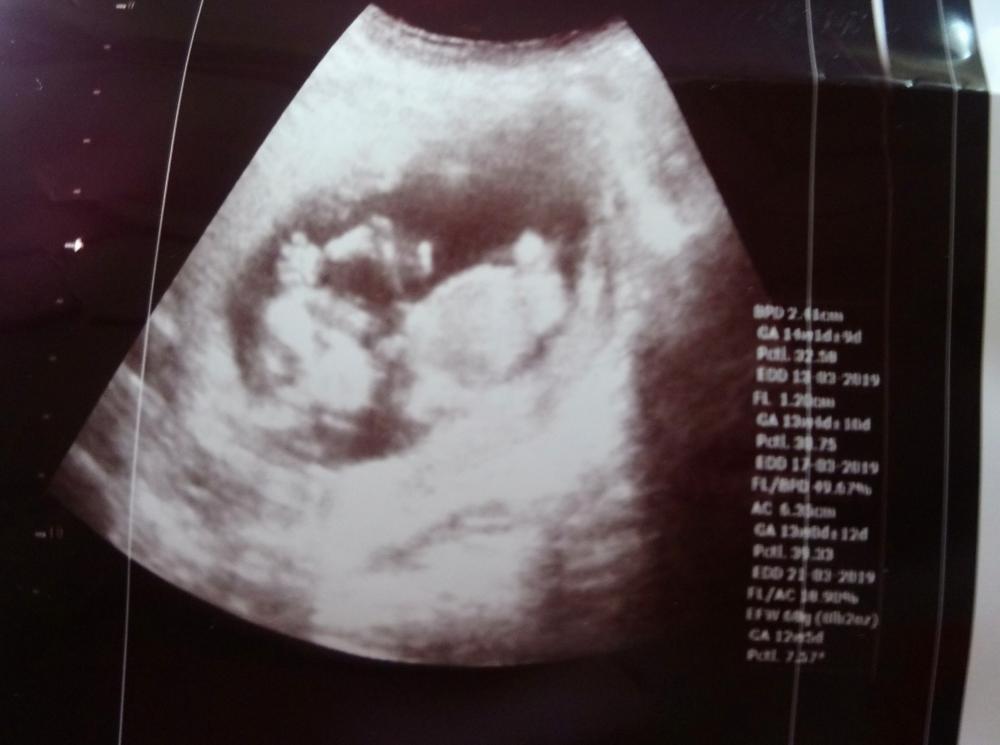

اليوم رحت عند الدكتورة عبير مشان تصرفلي الإبر وعملت سونار وقال ممكن ولد قبل مايقول زوجي لاتقولي انا بالأسبوع 13 رح نزل الصور كنت كتير فرحانة لاني شفتو عم يتحرك وصورتلي ياه رافع ايدو 😊

بنات شوفولي مبين شي خاصة قلبي قسى وبنت السلطنة احس عندكن خبرة